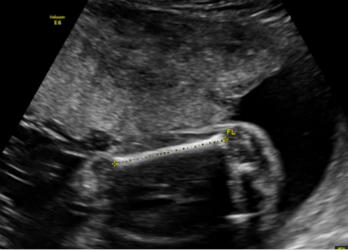

3.妊娠28周~32周超声检查;主要进行胎儿生长发育情况的评估、测量及部分胎儿结构畸形的筛查。

3.妊娠28周~32周超声检查:对一些在胎儿发育过程中才逐渐表现出来的胎儿畸形进一步筛查,以及对之前检查可能漏诊的畸形补漏。同时,观察这个时期胎儿的生长发育情况,监测有否胎儿宫内生长迟缓。